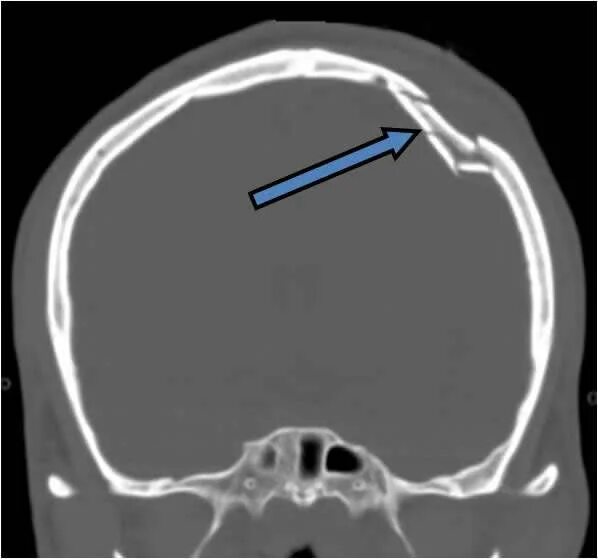

Оскольчатый перелом черепа